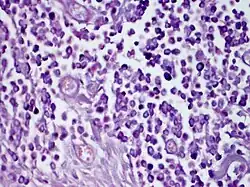

| Solitary mastocytoma. | |

Based on the lesion's shape, the existence of a positive Darier sign, and the lack of systemic involvement, the diagnosis is primarily clinical.[19] If necessary, a skin biopsy can be used to confirm the diagnosis by demonstrating a KIT mutation in the lesional skin and confirming mast cell infiltration in the dermis.[2]